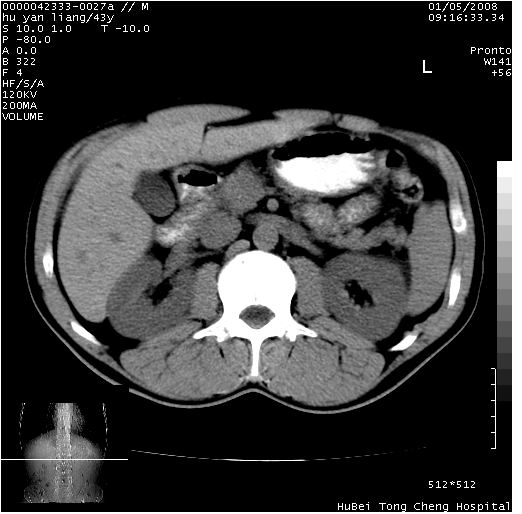

患者 男,43岁。右上腹不适1年余。既往有“肝右叶肝脓肿”病史,经保守治疗后痊愈。

b超提示:1)肝右叶肝内胆管结石。2)肝右叶占位性病变待排。

上中腹部ct轴位平扫+增强扫描(层厚10mm,螺距1.0,重建间隔10mm),图像如下:

肝右叶钙化灶,考虑为肝脓肿后遗症。

肝脓肿后遗症,肝右叶钙化。